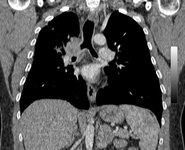

Malignant endobronchial obstruction on multidetector chest CT: coronal reconstruction demonstrating right mainstem malignant obstruction

From the collections of Jose Fernando Santacruz MD, FCCP, DAABIP and Erik Folch MD, MSc; used with permission